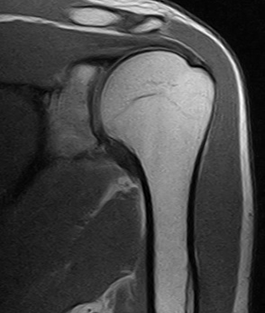

様々な部位や疾患の検査において幅広い診断情報を得るために、当院では整形外科の検査に特化した最新のオープン型MRIを導入しております。

X線一般撮影では判別しづらい骨折や骨のダメージ、靭帯など軟部組織の精査が可能です。

背骨や関節の検査に特化したMRIです。独自開発された患部ごとに対応した高感度専用コイル(体内からの信号を受信するアンテナ)と最新の画像技術により、超電導型にせまる高画質を実現しています。